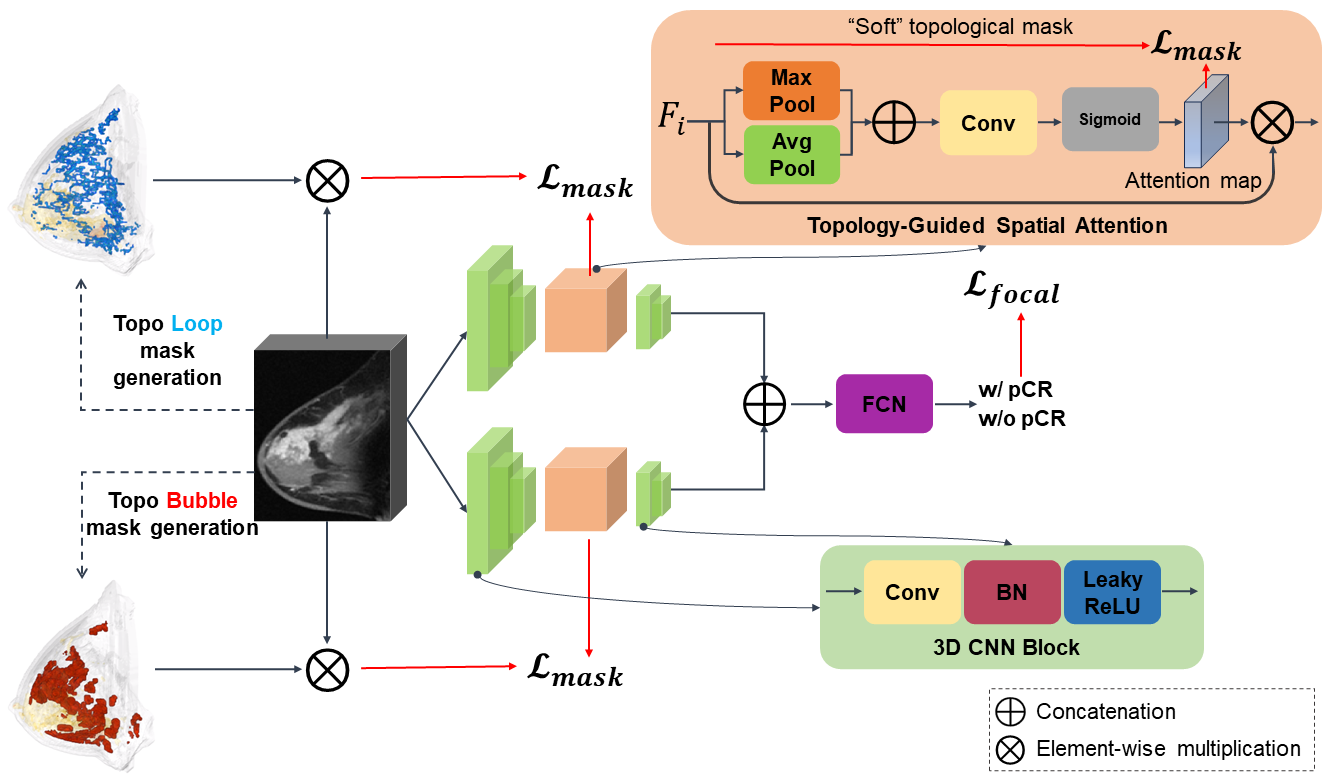

We propose a topological method to extract topological structures of high saliency, approximating tissue structures, and utilize these extracted structures as auxiliary information to train a deep convolutional network with raw MRI inputs. Although we focus on training our model for the pCR prediction task, the methodology is versatile enough to be generalized for other tasks. Our approach is detailed in Fig. 3.

We first compute salient topological structures from the input image utilizing persistent homology theory. Topological structures of dimensions 1 and 2, i.e., loops and bubbles, can both correspond to important tissue structures. 1D topological structures capture curvilinear structures such as ducts, vessels, etc. 2D topological structures represent voids enclosed by the tissue structures and their attached glands. These topological structures directly delineate the critical tissue structures with high biological relevance. Thus we hypothesize that by focusing on these tissue structures and their affinities, we can gain pertinent contextual information for pCR prediction.

Subsequently, we introduce a novel 3D CNN framework tailored for breast MRIs that integrates topological structures via an attention mechanism. Our method constructs a custom loss function, combining a mask-guided loss and a refined classification loss, the latter based on focal loss as detailed in Lin et al. [37]. Notably, we identify two types of pertinent topological structures: loops and bubbles. Our network consists of two separate 3D CNNs, treating the two types of topological structures separately. Empirical evidence demonstrates that both topology types capture complementary structural signatures, proving essential for achieving optimal predictive performance.

Although the persistence diagram has been used for topological analysis in various dataset [27, 74, 78], it only records limited information, i.e., the times at which these topological structures appear/disappear. We hypothesize that a detailed geometric realization of these topological structures can be crucial for learning from images. To this end, we propose extracting these topological structures and integrating them into the learning process. As shown in Fig. 3, we extract loops (blue) to denote 1D topological structures and bubbles (red) for 2D topological structures. These structures are then used to guide the attention mechanism within the neural network.

To incorporate the generated topological structures into a deep learning classifier, we propose a novel topology-guided spatial attention module. Using a new loss that enforces the spatial attention map to be similar to the topological structures, we direct the model’s attention to the vicinity of breast tissues, thus achieving better prediction power. We first explain the generation of the topological mask, i.e., the union of all topological structures. Next, we explain how to use the topological masks to guide the attention of a deep neural network.

Generating topological masks. We initiate by extracting topological structures which are represented as sets of voxels. The union of these voxel sets is then used to form a mask that closely approximates biologically pertinent regions.

Topology-guided spatial attention. In vision-related tasks, spatial attention creates an attention map by harnessing the inter-spatial relationships among features [76]. In the realm of medical tasks, attention mechanisms have been effectively applied to medical image registration [64] and drug response prediction [21]. TopoTxR employs this type of attention to focus on topological structures. Unlike traditional spatial attention, mask-guided attention integrates masks to sharpen model focus which offers a more targeted approach [53]. With these masks defining explicit regions of interest, the model is adept at selectively concentrating on the most pertinent sections, while minimizing attention to regions that might contain noise or are of lesser significance based on mask guidance. This not only streamlines the training process but also bolsters performance. Our work introduces the topology-guided spatial attention module, as illustrated in Fig. 3. This module generates a spatial attention map, which is supervised by the aforementioned ”soft” topology masks.

We employ distinct 3D CNN networks for both the 1D and 2D branches, each maintaining the same architecture. Every 3D CNN is structured with five 3D convolution layers, with each layer being succeeded by a batch normalization layer and then a LeakyReLU activation. In the topology-guided attention module, the feature maps from the third convolution layer, referred to as (where signifies the branch dimension), are initially processed through both average-pooling and max-pooling operations independently. These pooled results are then concatenated, serving as input for a subsequent convolution layer. The convolution layer’s output passes through a sigmoid activation function ,resulting in the generation of attention maps, denoted as where .

To emphasize the regions highlighted by the attention maps, we conduct an element-wise multiplication of and . The product, , is channeled as input into the fourth layer of the 3D CNN. Outputs from both 3D CNN branches are subsequently vectorized and concatenated. This combined output feeds into the fully convolutional network, culminating in a binary classification. In our ablation study, we further investigate the optimal layer from which to source input for the attention module.

The generation of spatial attention masks is guided by ”soft” topological masks. This guidance ensures their similarity is captured through a mean squared error (MSE) loss. The loss for our topology-guided spatial attention module, denoted as , is defined as:

where and represent the topological masks for 1D and 2D dimensions, respectively.

The focal loss enforces a well-balanced classification performance [37]. The focal loss, denoted as , is defined as:

In this context, is the ground truth of the classification, while indicates the probability of the model prediction. Focal loss incorporates two hyperparameters: and . The parameter is responsible for balancing the weights of positive and negative sample losses, whereas amplifies the loss contribution from hard samples. The mask loss and focal loss together form our overall loss function:

where is a hyper-parameter.